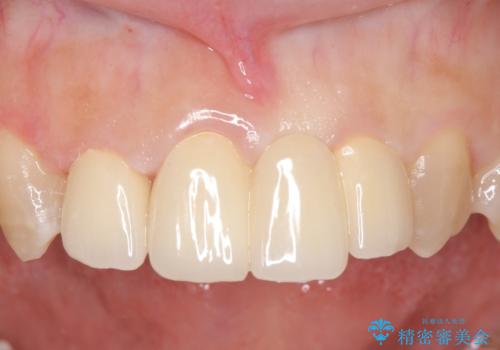

- 前歯の歯並びや色が気になるといらっしゃった方の症例です。

前歯4本をオールセラミッククラウンで補綴することで、歯の並びや色の改善を行いました。

今回用いたオールセラミッククラウンはジルコニアフレームという白い素材の上にセラミックを盛っているため、審美性が非常に高いのが特徴です。